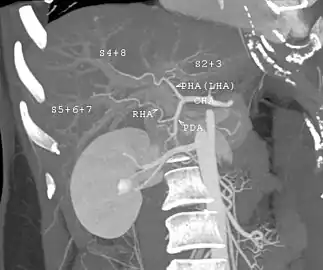

With the recent advances of noninvasive imaging, living liver donors usually have to undergo imaging examinations for liver anatomy to decide if the anatomy is feasible for donation. The evaluation is usually performed by multidetector row computed tomography (MDCT) and magnetic resonance imaging (MRI). MDCT is good in vascular anatomy and volumetry. MRI is used for biliary tree anatomy. Donors with very unusual vascular anatomy, which makes them unsuitable for donation, could be screened out to avoid unnecessary operations.